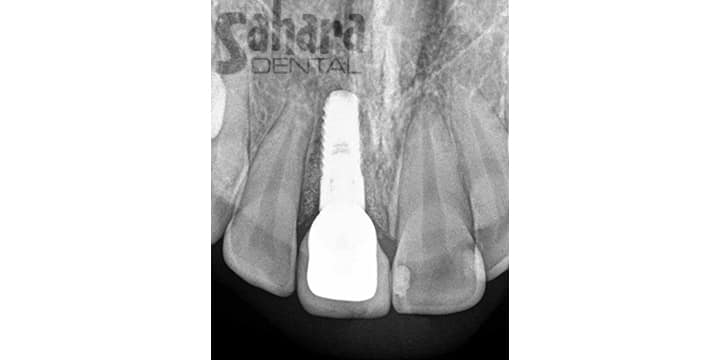

Natural-Looking Front Tooth Implant

Take a look at this smile transformation by Dr. Jamal in Pomona, California. The patient was missing a front tooth in the "before" photo. After receiving a dental implant, her smile looks complete and natural. Dr. Jamal helped restore both function and confidence with this life-changing treatment.